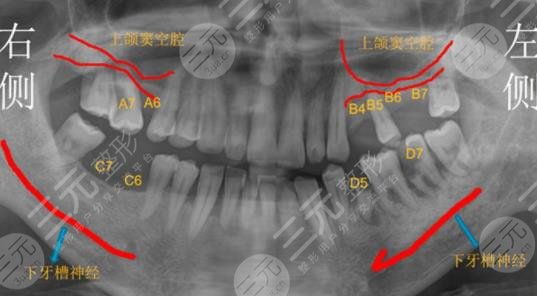

一次在户外骑车的时候出现了牙齿的脱落,右侧总共去了5颗牙,牙齿缺失之后只能到医院做牙齿种植治疗。牙齿种水的价格略贵,到医院检查之后医生说可以分两次进行,第1次种植两颗,过了几个月之后再种植剩下的两颗。

我选择的是一款进口的牙体,材料价格是中等的。在去医院的路上我还是很紧张的,因为第一次去做这也的手术,但是在牙齿种植的过程当中,医生先是打了局麻药物,手法也十分温柔,然后就开始进行操作,主要是将牙槽骨断开一个洞,然后再将假牙放里面。牙齿种植之后和自己的真牙并没有什么两样,较为的结实,平时吃一些坚硬的食物也是可以的。由于进行了两次的治疗,总共下来接近有一年的时间。牙齿痛的价格真的还挺贵的,所以平时一定要爱护自己的牙齿。不得不说浙江大学医学院附属口腔医院技术还是很过关的。下面我就把价目表放在下面了,供大家参考一下。